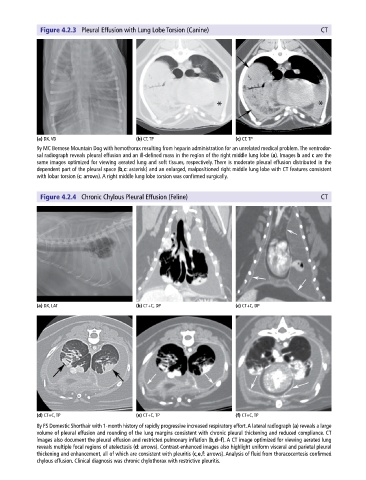

Figure 4.2.3 Pleural Effusion with Lung Lobe Torsion (Canine) CT

(a) DX, VD (b) CT, TP (c) CT, TP

9y MC Bernese Mountain Dog with hemothorax resulting from heparin administration for an unrelated medical problem. The ventrodor-

sal radiograph reveals pleural effusion and an ill‐defined mass in the region of the right middle lung lobe (a). Images b and c are the

same images optimized for viewing aerated lung and soft tissues, respectively. There is moderate pleural effusion distributed in the

dependent part of the pleural space (b,c: asterisk) and an enlarged, malpositioned right middle lung lobe with CT features consistent

with lobar torsion (c: arrows). A right middle lung lobe torsion was confirmed surgically.

Figure 4.2.4 Chronic Chylous Pleural Effusion (Feline) CT

(a) DX, LAT (b) CT+C, DP (c) CT+C, DP

(d) CT+C, TP (e) CT+C, TP (f) CT+C, TP

8y FS Domestic Shorthair with 1‐month history of rapidly progressive increased respiratory effort. A lateral radiograph (a) reveals a large

volume of pleural effusion and rounding of the lung margins consistent with chronic pleural thickening and reduced compliance. CT

images also document the pleural effusion and restricted pulmonary inflation (b,d–f). A CT image optimized for viewing aerated lung

reveals multiple focal regions of atelectasis (d: arrows). Contrast‐enhanced images also highlight uniform visceral and parietal pleural

thickening and enhancement, all of which are consistent with pleuritis (c,e,f: arrows). Analysis of fluid from thoracocentesis confirmed

chylous effusion. Clinical diagnosis was chronic chylothorax with restrictive pleuritis.